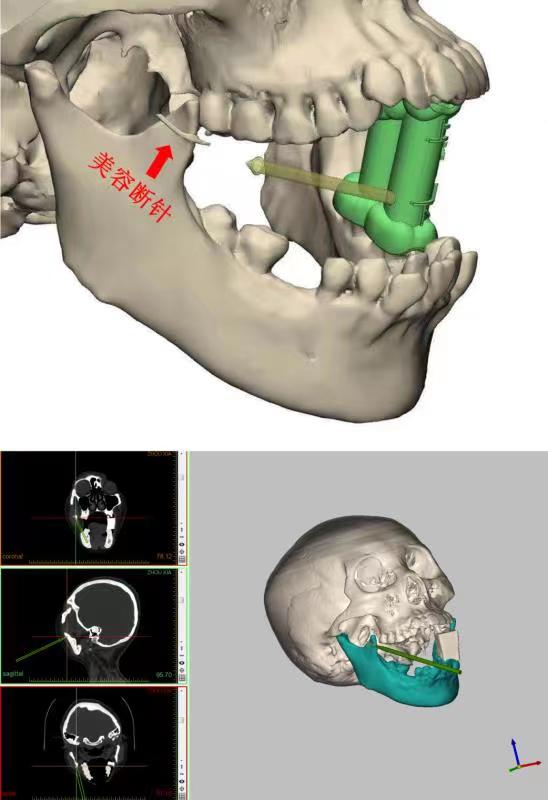

综合考虑患者的情况后,专家组李祖兵教授、李智教授决定运用目前临床先进的3D打印和计算机导航技术从口内入路微创取出断针。经过专家反复讨论,专门设计了一款3D打印的咬合导板用于维持术前CT检查和手术过程中相一致的开口位,以确保异物的相对位置不发生改变,同时利用计算机辅助导航精准定位断针位置。

8月27日,在数字化3D咬合导板和计算机导航的辅助下,医生精准定位断针位置,通过口内1厘米的切口,在肌肉深部找到并取出了1.5cm长的“闯祸”断针,手术仅历时半个小时。